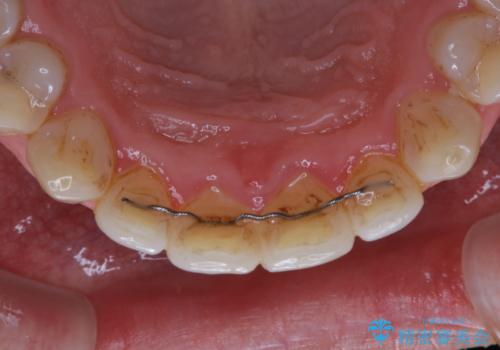

全体的にプラークや歯石が付着していて、歯肉炎が見られました。

状態に合った専門的な器具を使用して、歯質や歯肉へのダメージを抑えながらPMTC(自費クリーニング)60分コースを行いました。矯正治療後の保定装置がワイヤーの場合、フロス・糸ようじが通せないこと、歯ブラシがしずらいことなどにより、歯石プラークなどが付着しやすくなります。そのため専門的な器具による細かいケアを行うことがとても大切です。